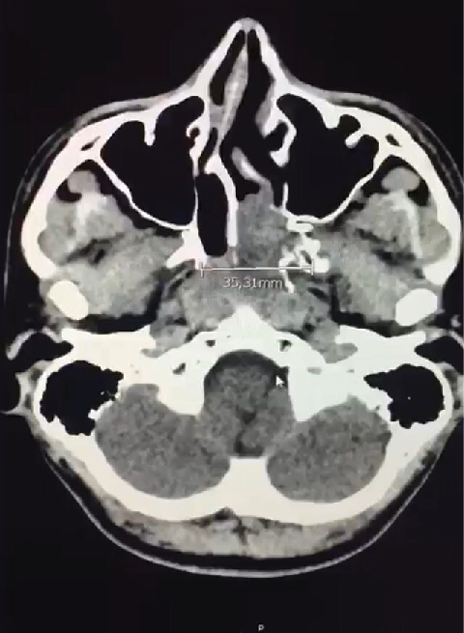

Paciente del género masculino de 19 años de edad sin antecedentes de importancia, quien consulta por cuadro clínico de 7 días de evolución caracterizado por cefalea hemicraneada izquierda no pulsátil sin irradiación asociado a otalgia izquierda y sensación de opresión ocular izquierda. Quien previamente había consultado extra-institucionalmente con manejo analgésico sin mejoría, consulta nuevamente por aumento del dolor clasificado 10/10 en la escala análoga del dolor, sin síntomas visuales, sin sangrado nasal y sin alteraciones neurológicas. A la revisión por sistema informa episodios de alteración del olfato desde los 7 años de edad y único episodio de epistaxis en fosa nasal izquierda auto limitado a los 16 años de edad. Como único antecedente patológicos rinitis alérgica intermitente y antecedente toxico una aparente exposición al polvo de madera; al examen físico la rinoscopia anterior mostró hipertrofia de cornetes bilateral y mucosa pálida, sin masas en región anterior. Se solicito tomografía axial computarizada cerebral con hallazgos de masa de densidad de tejidos blandos que ocupa la coana izquierda, infiltra parcialmente la región posterior de la fosa nasal de este lado, erosiona la apófisis pterigoides. Tiene diámetros aproximados de 47 x 34 x 35 mm en los ejes craneocaudal, rostro dorsal y axial respectivamente (Figura 1).

Figura 1. Tomografía axial computarizada con lesión expansiva en fosa pterigomaxilar izquierda. Fuente: Hospital Militar Central de Bogotá.